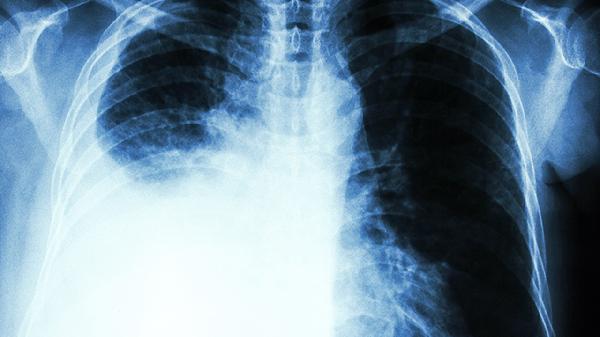

肺癌晚期患者除规范用药外,需保持高蛋白饮食如鱼肉、蛋奶,适量补充维生素D。每日进行温和活动如散步,避免剧烈运动。定期复查胸部CT评估疗效,出现咯血、持续胸痛等症状应立即就诊。心理疏导与疼痛管理同样重要,家属应给予充分情感支持。